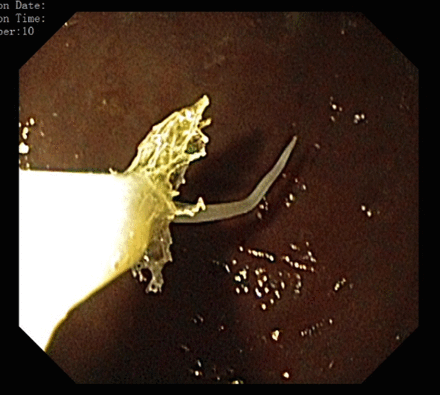

Luego de realizarle una serie de exámenes, los resultados del laboratorio mostraron leucocitosis leve, por lo que le realizaron una endoscopia para dar con el origen de este problema. Se trataba de la larva Anisakiasis ubicada en estómago del hombre, la cual estaba unida a una superficie de mucosa inflamada e hiperémica.

Posteriormente, el parásito se eliminó con una red de Roth y los síntomas del paciente desaparecieron inmediatamente.